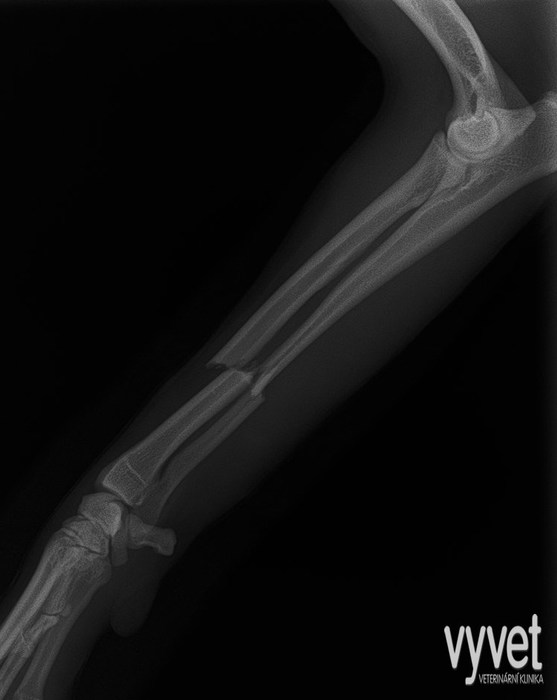

Nejčastějším problémem dlouhých kostí jsou zlomeniny (fraktury)

Rozdělujeme je do několika skupin podle charakteru, množství fragmentů, průběhu linie lomu, dislokace, stability atd.

Je mnoho popsaných metod fixací fraktur. Neinvazivní metodou je přikládání fixačních obvazů a kastů. Tento typ fixace však není ideální, protože nejsme schopni u zvířat zabezpečit dostatečně dlouhou dobu klidu pro srůst kosti. Ideální metodou je invazivnější přístup a to chirurgická repozice s následnou fixací osteosyntetickým materiálem.

Na našem pracovišti používáme zejména ploténky a hřeby.